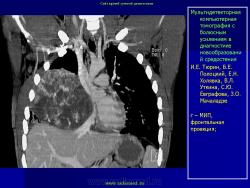

Средостение.  "Опухолевый рост".